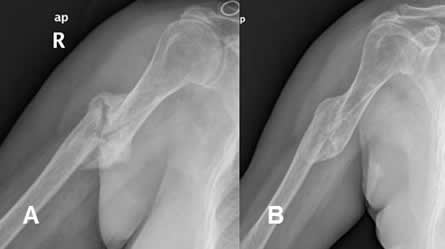

Fig 130 A. Mala consolidación.

A: Rx AP: Fractura en la diáfisis humeral, con callo óseo hipertrófico.

B: Rx AP. Completa consolidación, pero con fragmentos cabalgados.